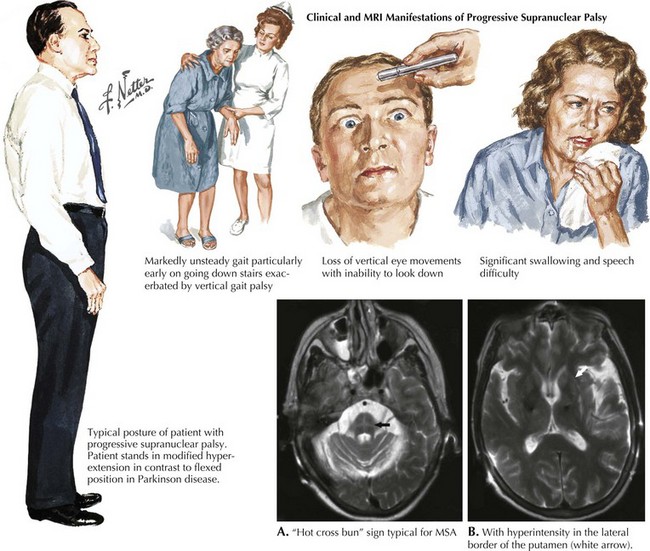

2. Paralisia Supranuclear Progressiva (PSP)

- Causa queda frequente, rigidez principalmente no pescoço, alterações nos movimentos dos olhos (dificuldade de olhar para cima ou para baixo) e dificuldade na fala e deglutição.